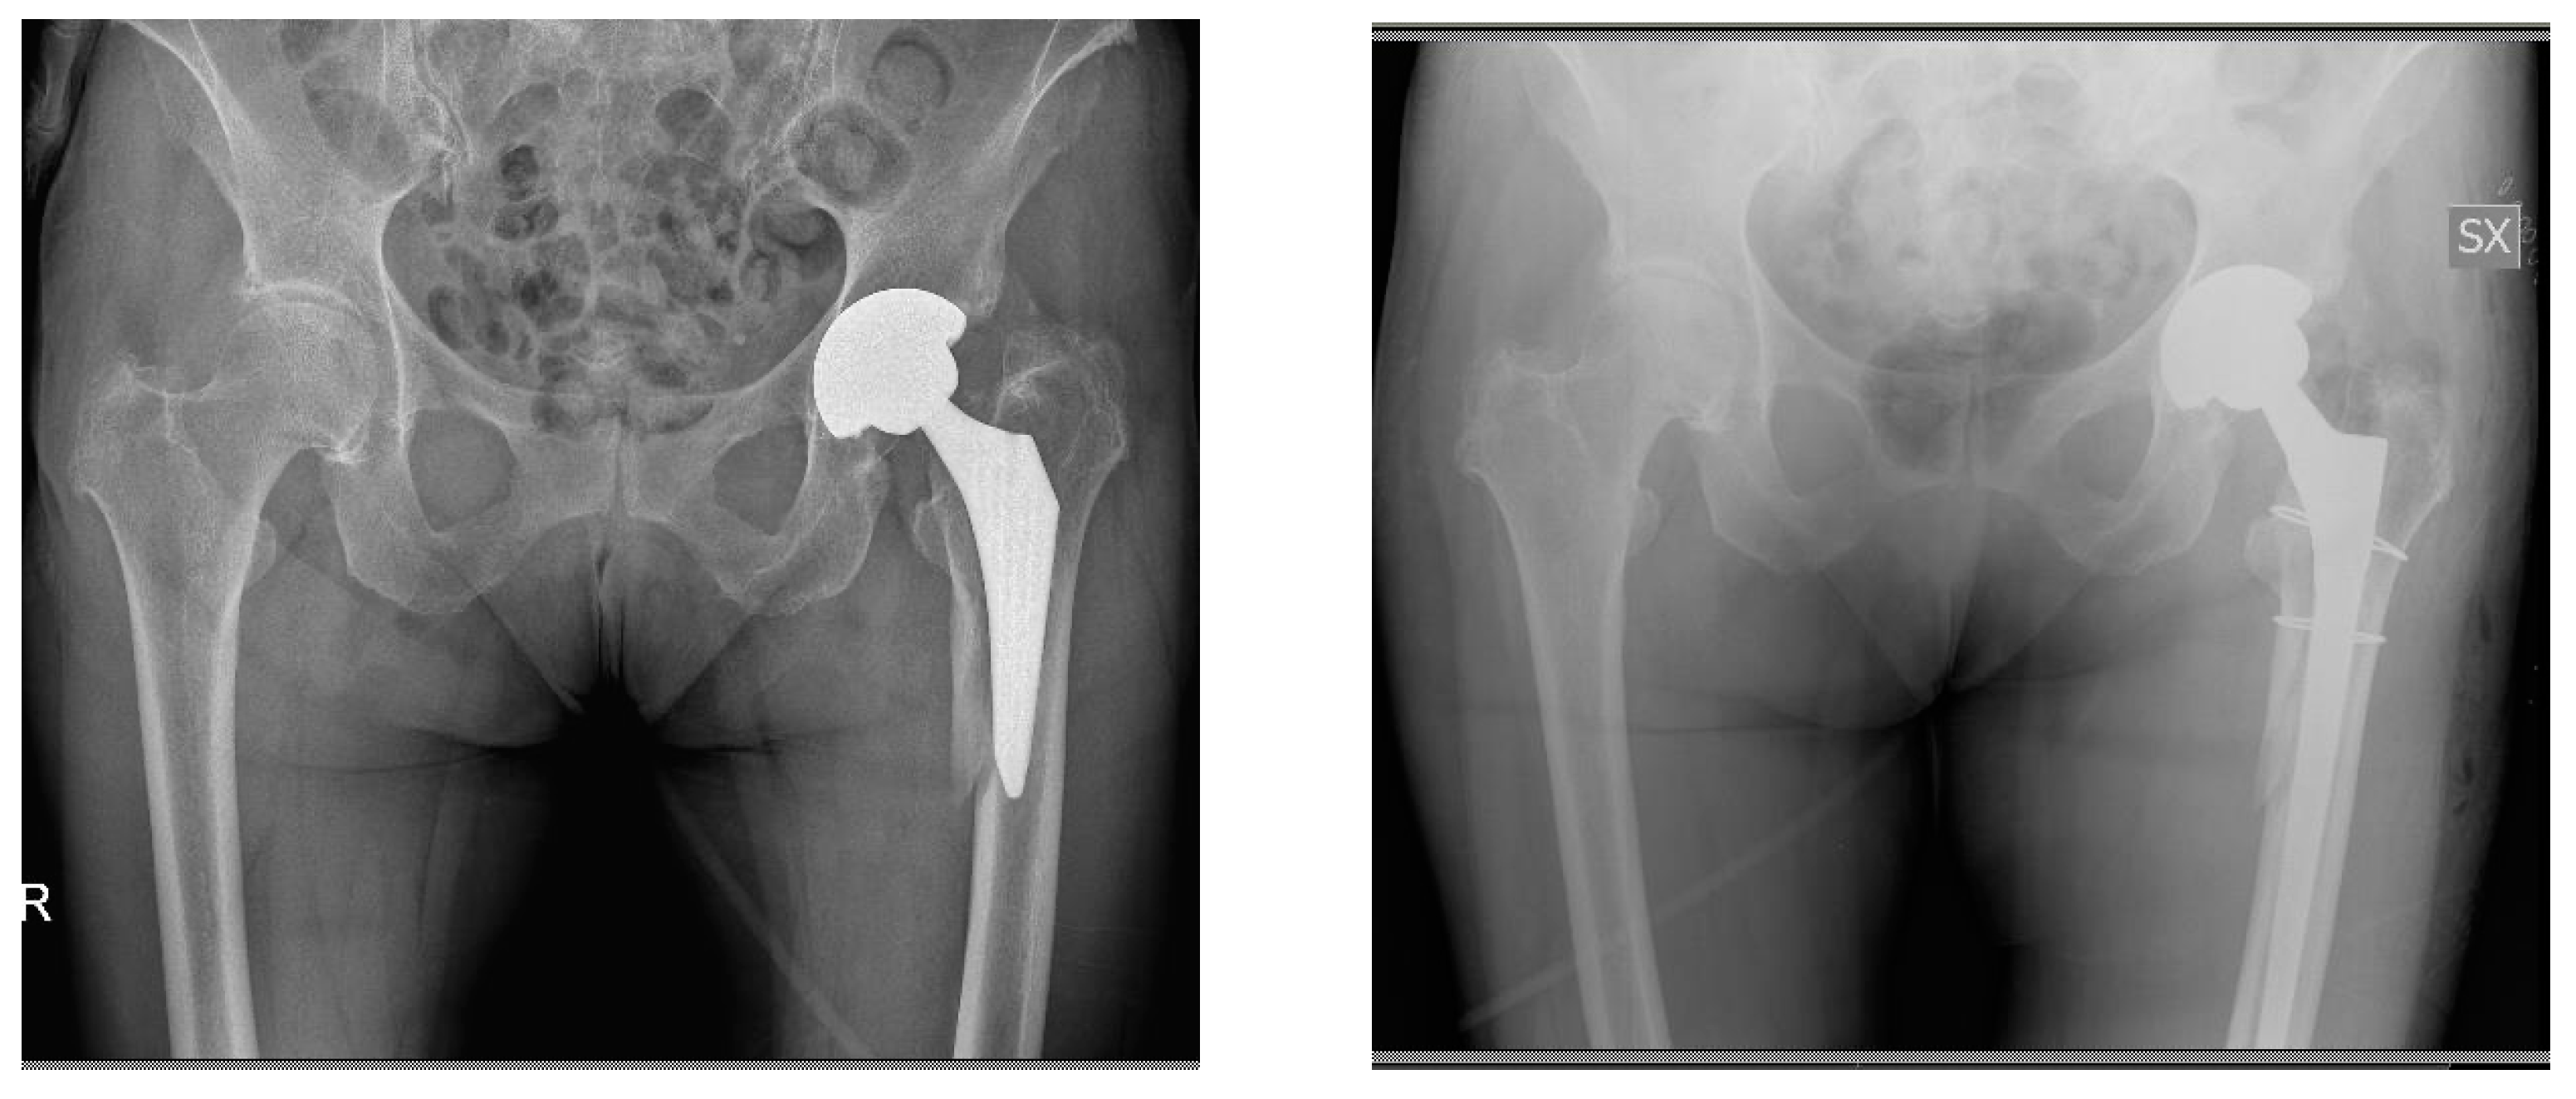

Revision of Failed Short Stems in Total Hip Arthroplasty

2.2. Surgical Technique